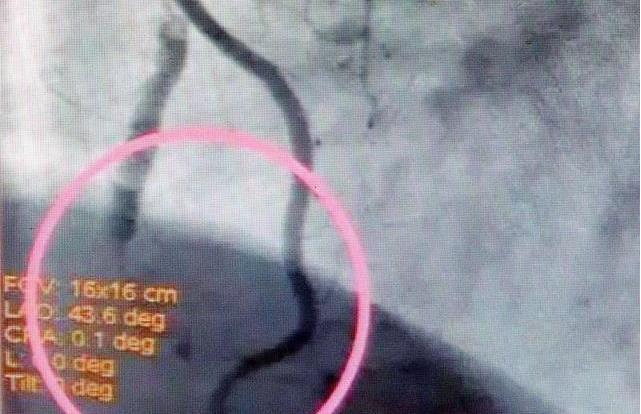

- 动脉瘤和动静脉畸形